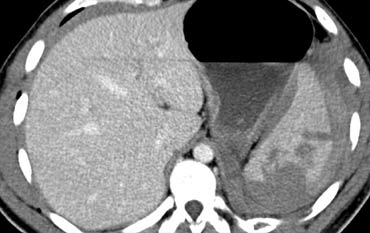

Trước tiên hãy quan sát các hình ảnh bên trái của bệnh nhân bị chấn thương gan.

Các dấu hiệu CT trong trường hợp này là gì?

Các dấu hiệu bao gồm:

- Tụ máu dưới bao gan lớn hơn 10 cm (tức là tổn thương độ 4)

- Vùng ngấm thuốc cản quang (contrast blush) (mũi tên)

- Không có tràn máu ổ bụng kèm theo

Vì vậy, mặc dù có thoát thuốc cản quang, bệnh nhân này sẽ được điều trị bảo tồn (không phẫu thuật) và có thể có tiên lượng tốt, do không có chảy máu vào khoang phúc mạc.

Thoát thuốc cản quang có ý nghĩa đặc biệt quan trọng, nhất là khi kết hợp với tràn máu ổ bụng.